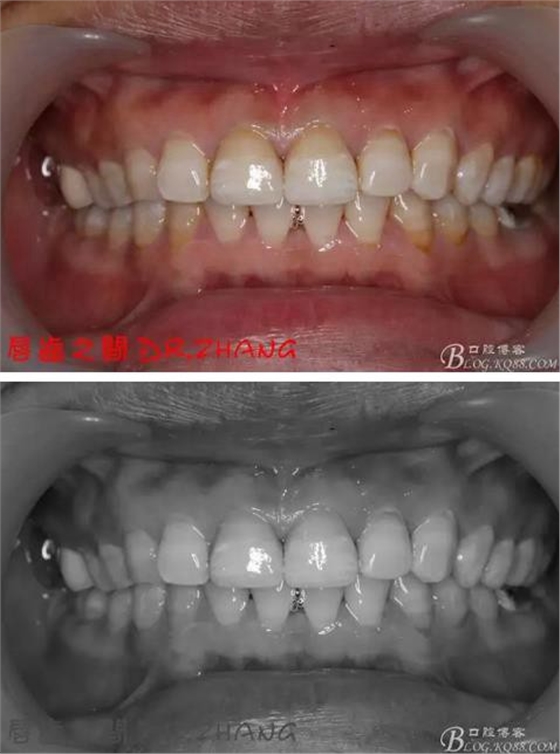

復(fù)診:臨時(shí)牙良好 患者自訴無(wú)不適癥狀 去除臨時(shí)修復(fù)體 排齦 清理牙面 試戴全瓷修復(fù)體后粘結(jié) 常規(guī)醫(yī)囑 不適隨診

總結(jié):沒(méi)有術(shù)前照片 預(yù)備牙體過(guò)長(zhǎng) 顏色還是有差距